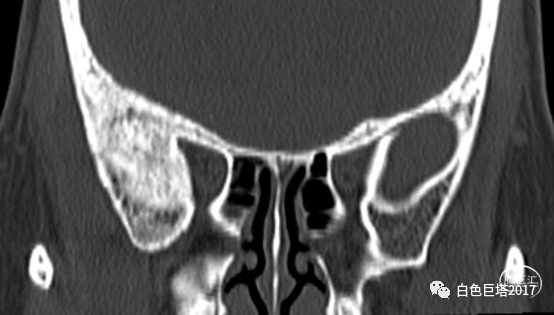

入院头颅CT检查提示右侧颞骨-眼眶后外侧壁骨质改变,眶内未见明显占位。报告考虑骨纤维异常增殖症可能性大。

3Dslicer重建可见眶后外侧壁骨质不均匀增厚,毛糙。